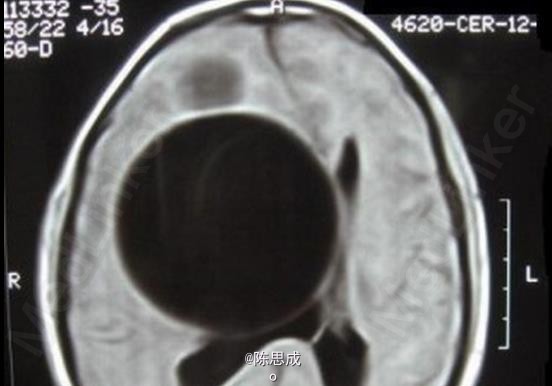

患者,男,12岁,因癫痫发作入院

既往健康 辅查MRI, T1和T2序列显示两个信号均匀的囊状影,囊肿推移挤压邻近的侧脑室

脑包虫病 处理;将包虫囊小心分离后完整摘除